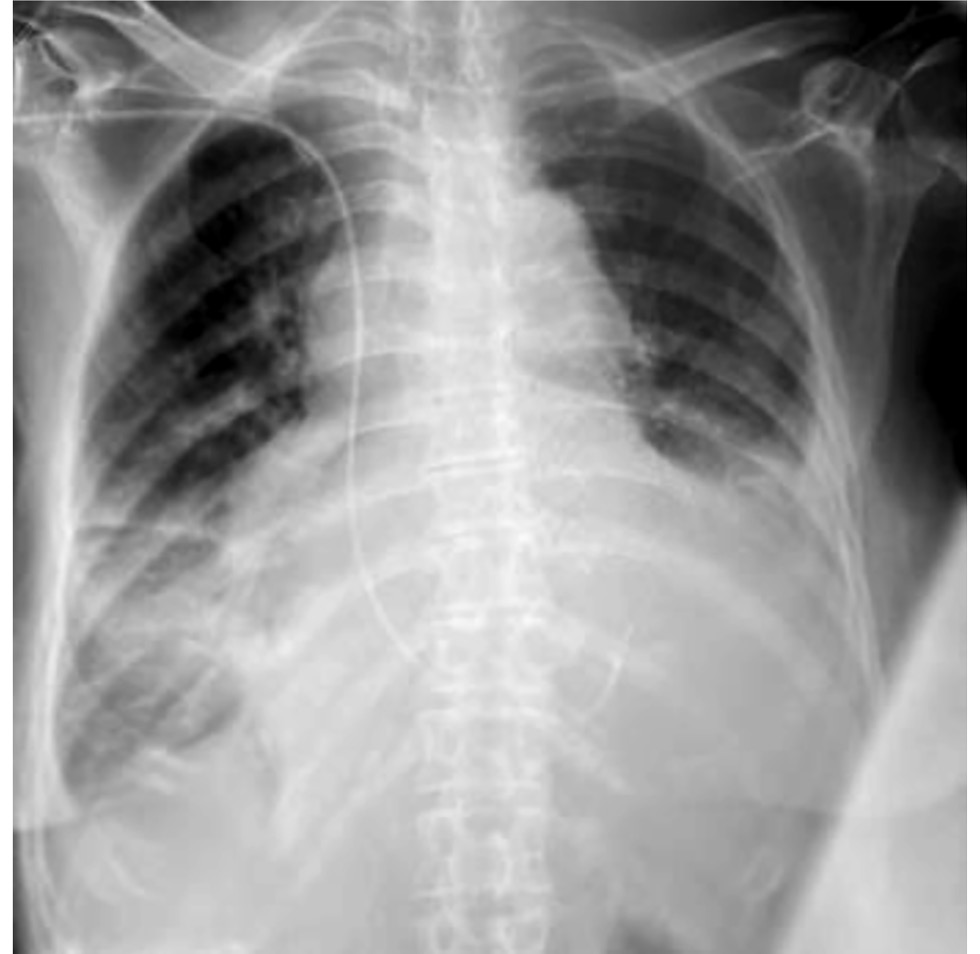

При госпитализации в отделение анестезиологии и реанимации ОККД общее состояние оценено как среднетяжёлое. По данным медицинской документации при осмотре пациентка астенического телосложения, кожные покровы и слизистые бледные, кожа влажная, периферические лимфатические узлы не увеличены, симметричные отёки стоп и голеней, частота дыхательных движений 26 в минуту, дыхание везикулярное, ослаблено, сухие единичные хрипы, перкуторный звук лёгочный, насыщение крови кислородом 93%, ритм сердца правильный с ЧСС 40 уд./мин, артериальное давление 105/70 мм рт. ст. На ЭКГ регистрировалась АВ-блокада III степени с замещающим ритмом на фоне синусовой тахикардии (118 уд./мин). Диагноз ИБС предположен в качестве наиболее вероятной причины АВ-блокады с учётом возраста и анамнеза болей в грудной клетке. Диагноз двусторонней пневмонии не снят с учётом сохраняющихся очагово-инфильтративных изменений в лёгочной ткани (рис. 4, 5). Установлен временный кардиостимулятор в режиме VVI с частотой стимуляции желудочков 60 в минуту. Продолжена терапия цефтриаксоном 1 г 2 р/сут внутривенно, назначен эноксапарин натрия 0,4 мл 2 р/сут подкожно.

Рис. 4. Рентгенограмма органов грудной клетки пациентки Б. от 31.01.2023.

Fig. 4. Chest X-ray of patient B. dated January 31, 2023.

Рис. 5. Рентгенограмма органов грудной клетки пациентки Б. от 01.02.23.

Fig. 5. Chest X-ray of patient B. dated February 1, 2023.